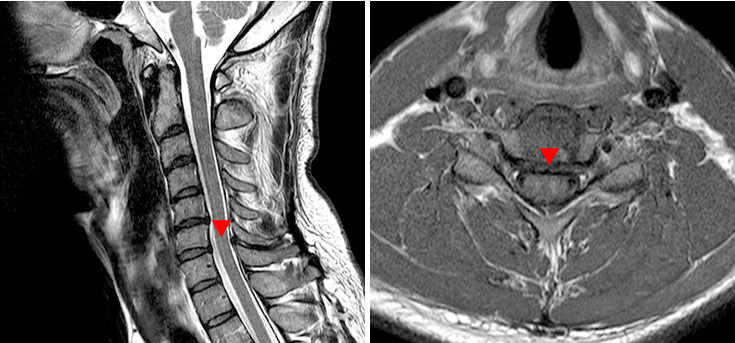

목디스크는 목 뼈 사이에 위치한 척수 신경이 압박을 받아 극심한 통증을 유발하는 질환입니다. 단순히 어깨목결림 뿐만 아니라 팔 저림, 손 저림, 만성 두통 등의 합병 증상까지 나타나 일상생활에 지장을 주게 됩니다.

급성 목디스크는 목 통증, 팔 저림을 호소하며 갑자기 나타나는 반면, 퇴행성으로 인한 만성 목디스크는 천천히 악화되어 목 통증 및 견갑골 사이 통증까지 악화되며 더 방치할 경우 신경이 눌러 발생하는 근육통 및 두통 등의 통증을 경험하게 됩니다.